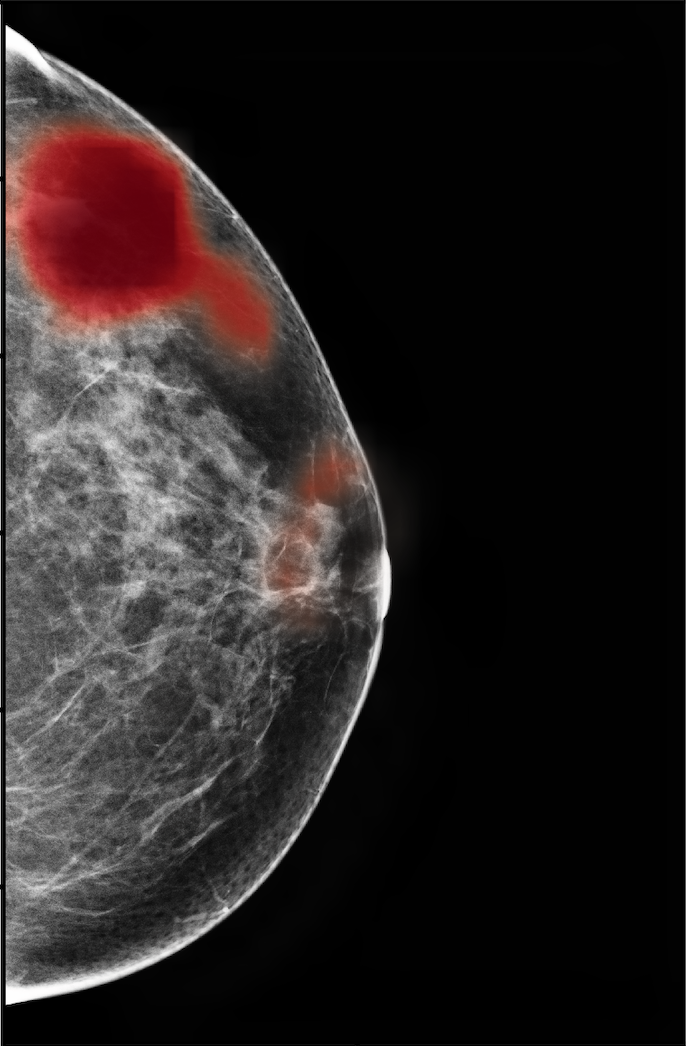

Screening mammography is inherently different from typical natural images from a few perspectives. First of all, as illustrated in Figure 1, regions of interest (ROI) in mammography images, such as masses, asymmetries, and microcalcifications, are often smaller in comparison to the salient objects in natural images. Moreover, as suggested in multiple clinical studies [72, 53, 73], both the local details, such as lesion shape, and global structure, such as overall breast fibroglandular tissue density and pattern, are essential for accurate diagnosis. For instance, while microcalcifications are common in both benign and malignant findings, their presence in a ductal distribution, such as in the third example of Figure 1, is a strong indicator of malignancy. This is in contrast to typical natural images where objects outside the most salient regions provide little information towards predicting the label of the image. In addition, mammography images are usually of much higher resolutions than typical natural images. The most accurate deep CNN architectures for natural images are not applicable to mammography images due to the limited size of GPU memory.

The NYU Breast Cancer Screening Dataset [78] includes 229,426 exams (1,001,093 images) from 141,472 patients.222Our retrospective study was approved by our institutional review board and was compliant with the Health Insurance Portability and Accountability Act. Informed consent was waived. Each exam contains at least four images which correspond to the four standard views used in screening mammography: R-CC (right craniocaudal), L-CC (left craniocaudal), R-MLO (right mediolateral oblique) and L-MLO (left mediolateral oblique). An example is shown in Figure 3.

For all exams matched with biopsies, we asked a group of radiologists (provided with the corresponding pathology reports) to retrospectively indicate the location of the biopsied lesions. This way we obtained the segmentation labels: where if pixel belongs to the benign/malignant findings. An example of such a segmentation is shown in Figure 3. In all experiments (except for experiments in Section 3.6 that assess the benefits of utilizing segmentation labels), segmentation labels are only used for evaluation. We found that, according to the radiologists, approximately of exams were mammographically occult, i.e., the lesions that were biopsied were not visible on mammography, even retrospectively, and were identified using other imaging modalities: ultrasound or MRI.

In Figure 7, we visualize saliency maps for four samples selected from the test set. In the first two examples, the saliency maps are highly activated on the annotated lesions, suggesting that our model is able to detect suspicious lesions without pixel-level supervision. Moreover, the attention is highly concentrated on ROI patches that overlap with the annotated lesions. In the third example, the saliency map for benign findings identifies three abnormalities. Although only the top abnormality was escalated for biopsy and hence annotated by radiologists, the radiologist’s report confirms that the two non-biopsied findings have a high probability of benignity and a low probability of malignancy. In the fourth example, we illustrate a case when there is some level of disagreement between our model and the annotation in the dataset. The malignancy saliency map only highlights part of a large malignant lesion with segmental coarse heterogeneous calcifications. This behavior is related to the design of : a fixed pooling threshold cannot be optimal for all sizes of ROI. The impact of is further studied in 3.6. This example also illustrates that while human experts are asked to annotate the entire lesion, CNNs tend to emphasize only the most informative regions. While no benign lesion is present, the benign saliency map still highlights regions similar to that in the malignancy saliency map, but with a lower probability than the malignancy saliency map. In fact, calcifications with this morphology and distribution can also result from benign pathophysiology [42].